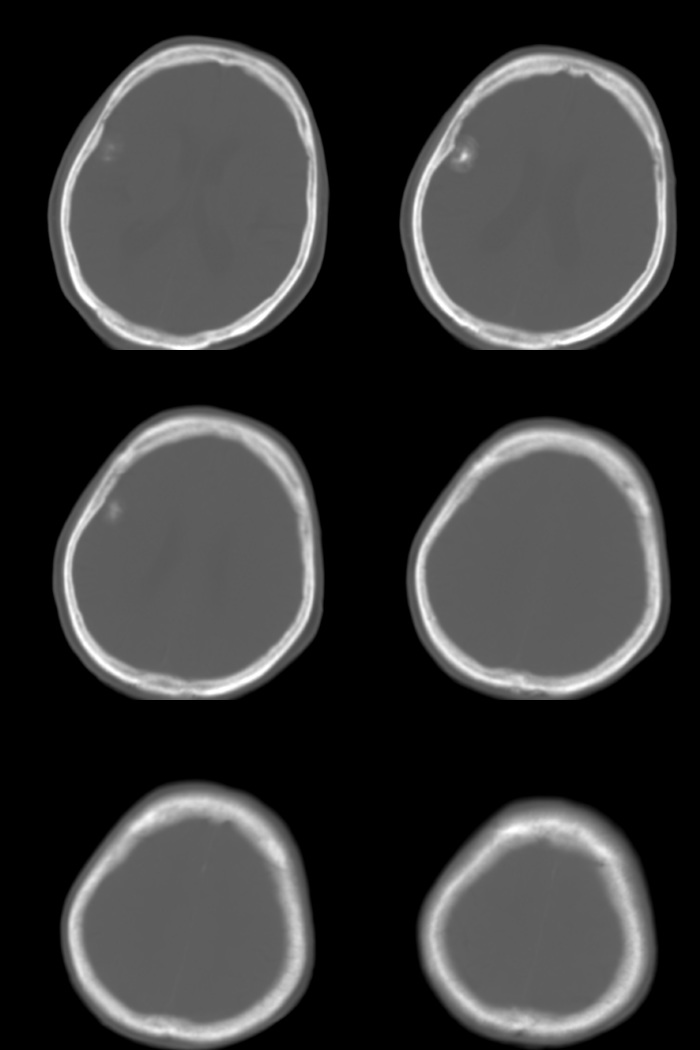

标题: CT17990:F76y,反复头昏。

76岁女性,反复头昏、头痛,余无不适。

诊断:右颞部钙化性脑膜瘤.

诊断依据:1.定位:脑外颅内--邻近脑沟增宽/脑组织受压内移/局部颅骨增生.

2.定性:良性--病灶边缘光整清楚/密度较高均匀/脑组织水肿不明显即占位效应不明显.

鉴别诊断:1.右颞骨内生骨软骨瘤/2.少突胶质细胞瘤/3.弥漫性星型细胞瘤.

考虑脑膜瘤可能性大,如果是骨软骨瘤应该是广基底与颞骨相连,本例没有发现;当然应该在病灶范围内行薄层扫描进一步查明其与颞骨的关系对诊断有帮助。